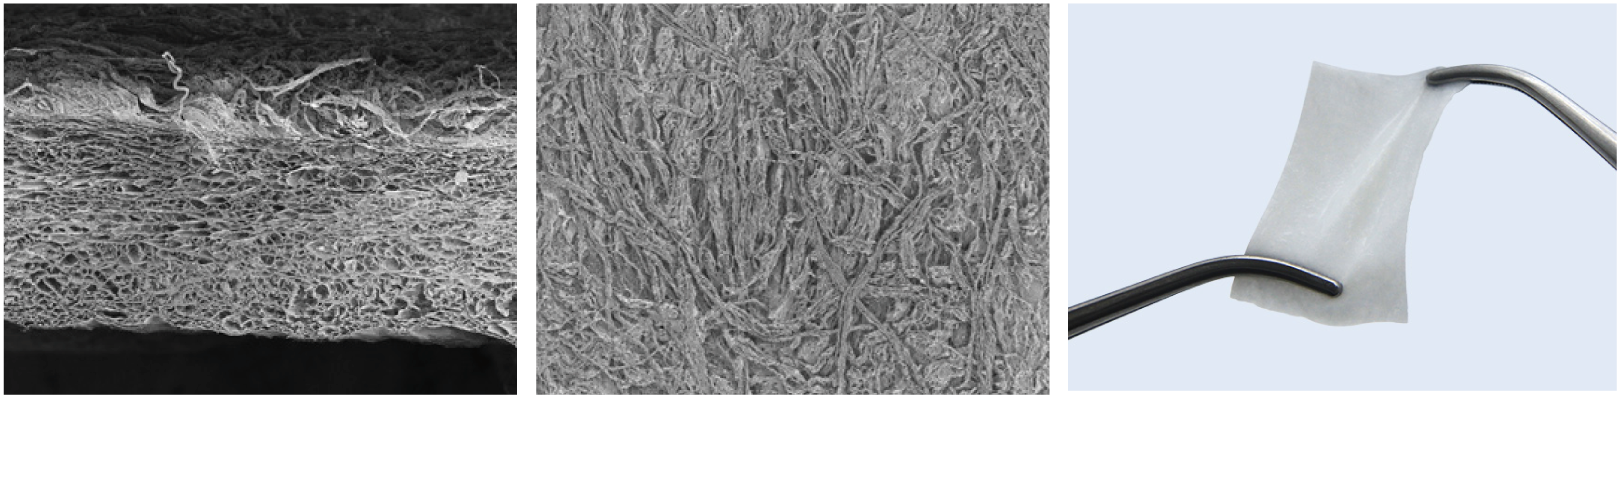

The natural structure of Straumann® XenoGraft

with interconnected porous granules facilitates the adhesion and invasion of bone forming cells

and results in complete integration of the implant due to the ingrowth of cells and blood vessels.

The natural structure of Straumann® XenoGraft

with interconnected porous granules facilitates the adhesion and invasion of bone forming cells

and results in complete integration of the implant due to the ingrowth of cells and blood vessels.